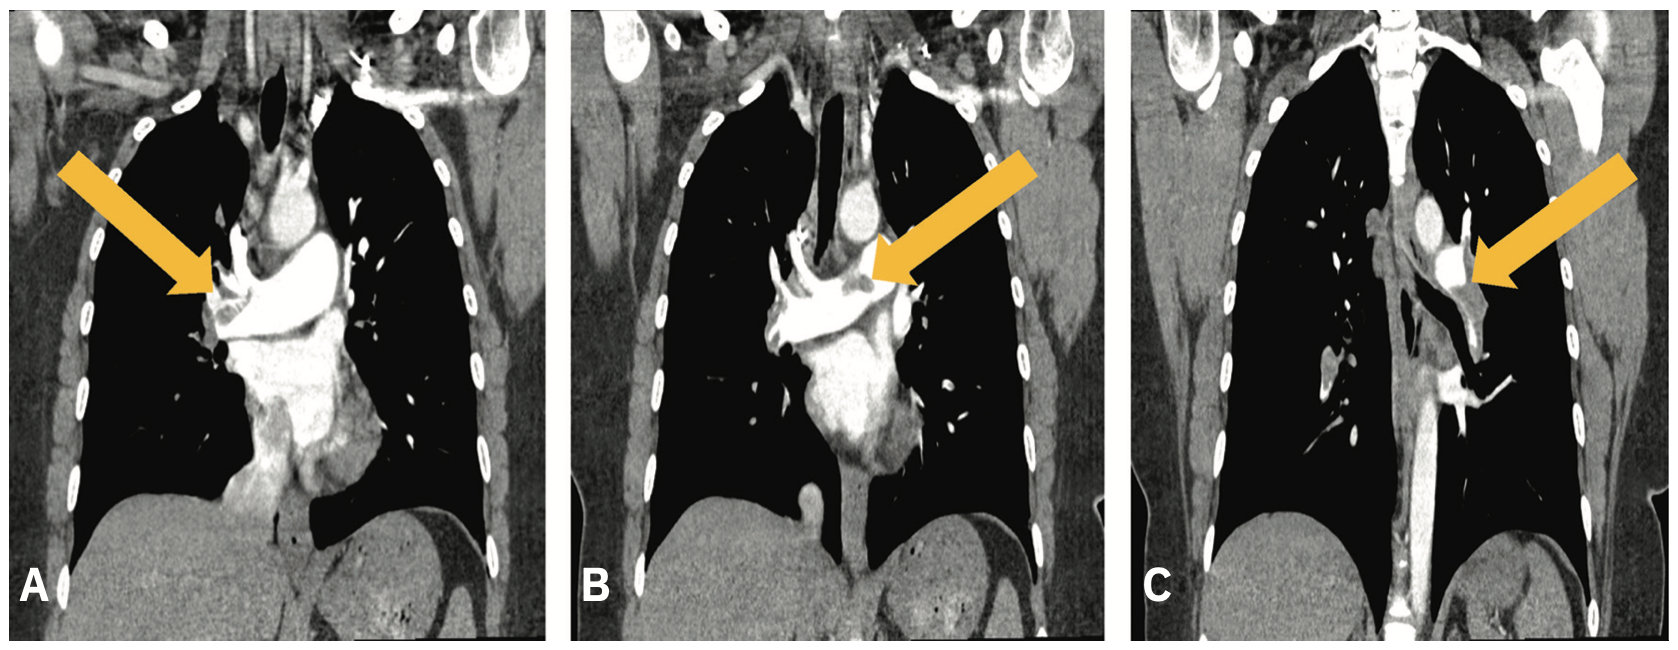

Pulmonary artery thrombectomy (A) The right panel shows the Triever20 Pulmonary Thrombectomy Anesthesia Surgery puts patients at increased risk for pulmonary embolism (pe). This section provides a comprehensive procedural report for pulmonary artery thrombectomy and thrombolysis. This operation leads to major clinical improvement and is a potential cure for a large majority for patients suffering from cteph [1]. Pulmonary thromboendarterectomy (pte) is the mainstay of therapy for patients with chronic thromboembolic pulmonary hypertension. Pulmonary Thrombectomy Anesthesia.